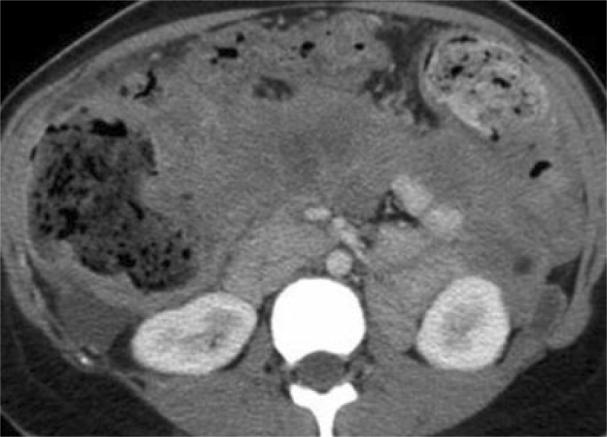

Acute pancreatitis can result in retroperitoneal fat necrosis, typically occurring in the peripancreatic region, with extension into the transverse mesocolon, omentum and mesenteric root. When evaluated with contrast enhanced computed tomography (CECT), acute peripancreatic post necrotic collections typically become lower in attenuation over time, and often appear as homogeneous fluid collections. Saponification as a complication of fat necrosis in patients with acute pancreatitis is a well recognized clinical entity. While retroperitonal fat necrosis is commonly seen on CECT, saponification is not a prominent imaging feature. We present a case of acute pancreatitis complicated by extensive saponification of fat throughout the retroperitoneum and peritoneal lining, mimicking carcinomatosis.

急性胰腺炎可导致腹膜后脂肪坏死,通常发生在胰腺周围区域,并可延伸至横结肠系膜、大网膜和肠系膜根部。当采用对比增强计算机断层扫描(CECT)评估时,急性胰腺周围坏死灶通常会随着时间推移而衰减降低,且常表现为均匀的液性病灶。作为急性胰腺炎患者脂肪坏死的并发症,皂化是一种广为人知的临床病症。虽然CECT上常见腹膜后脂肪坏死,但皂化并非显著的影像学特征。我们报告一例急性胰腺炎并发整个腹膜后和腹膜衬里广泛脂肪皂化的病例,其表现类似癌性腹膜炎。